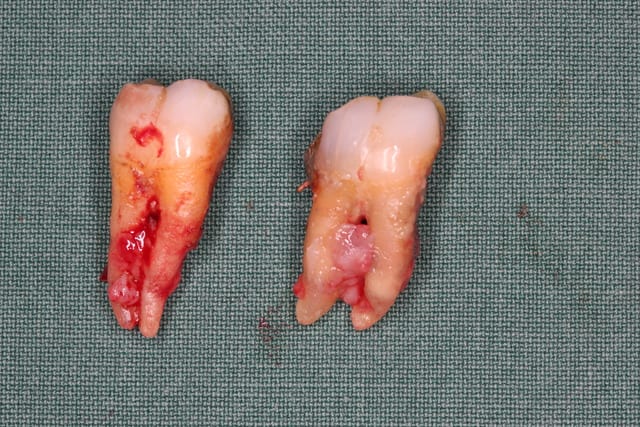

On a fait les PRfs et extractions des molaires maxillaires voici un mois

Et on vient d extraire le molaires inf avec PRFs ce jour

Pp

PS2 Message pour Olivier : quel traitement paro fais tu à cette patiente qd tu vois les pièces extractionnelles ?????

On est bien d'accord sur ce cas là, il n'y a malheureusement plus grand chose à faire.

Mais ces pertes parodontales ne sont pas survenues du jour au lendemain ! Ce qui est inquiétant est de savoir pourquoi rien n'a été fait auparavant ?!? La patiente n'était pas informée de son statut parodontal ou a-t-elle négligé tout ca ?

Ce qui est certain est que le risque d'avoir les mêmes problèmes autour de tes futurs implants est énorme !!

Extraire et implanter dans un cas pareil ce n'est vraiment pas le plus difficile. Le vrai challenge est de conserver l'ensemble sain.

Elle a subi une bonne vieille chir paro ce curetage à ciel ouvert...Un vrai miracle que je ne tente plus depuis des années

A mon humble avis, la maintenance ne sera que plus facile autour d implants propres et lisses d usinage qu autour de dents perclues de germes mais je te promets que je les tiens à l oeil quand ce genre de chose leur est arrivé

On notera un tabagisme intense d une durée de 20 ans qui n a en rien aidé bien sûr... Ce tabagisme fait partie du passé depuis 4 à 5 ans mais c était trop tard et trop mal mené sur le plan du suivi et stt cette chir paro à lambeau...